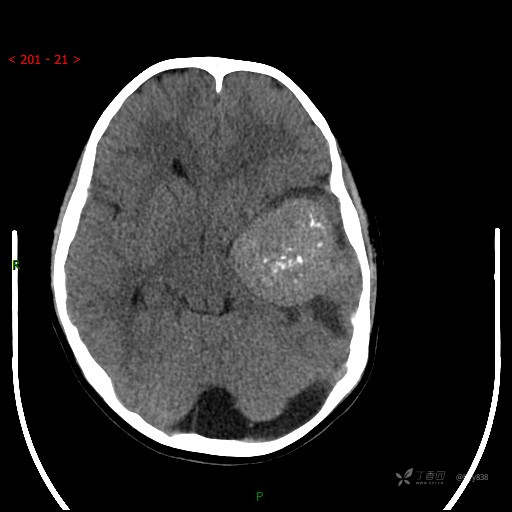

“典藏”病例分享。10岁儿童,头痛头晕一周余,CT、MRI 都有---结果公布~

简要病史:患者于一周前无明显诱因开始出现头痛头晕,无恶心呕吐,无肢体抽搐,无寒颤高热,无腹胀腹泻,无视力下降及视野缺损,上述症状休息后可稍缓解,未引起重视。 2天前患者头痛头晕不适加重,伴有恶心感,无呕吐,遂到当地人民医院行头颅CT检查示:左侧颞部占位性病变,今日家属为求进一步治疗,来我院门诊求治。门诊拟“左侧颞部占位性病变”收入我科。 患病以来,患者精神、饮食、睡眠尚欠佳,大小便如常,体力体重无明显变化。

临床诊断:左侧颞部占位

颅脑CT扫描